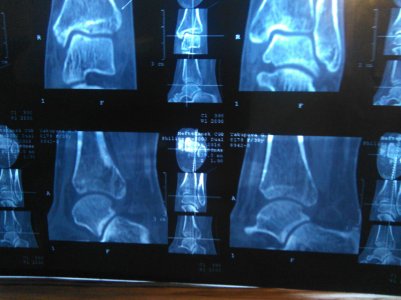

16 марта МРТ заключение: МР- картина консолидирующегося краевого косого перелома дорзальных отделов медиальной лодыжки /без смещения - перелом пилона тип В1 по АО/; остеоартроза голеностопного сустава и стопы: минимального синовита голеностопного сустава. Признаки отека мягких тканей области голеностопного сустава. (фото № 2)